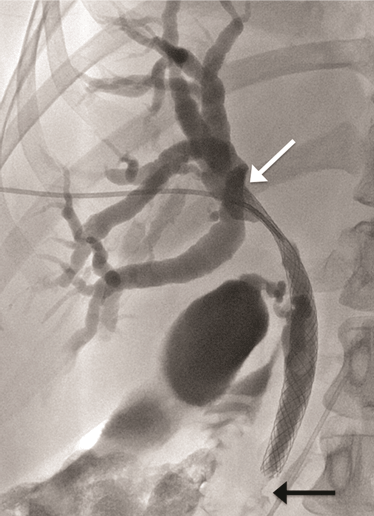

A 52-year-old female presented to her general physician with a four-month history of right upper quadrant discomfort and was referred for an outpatient abdominal ultrasound scan. This revealed intrahepatic duct dilatation and subsequent computed tomography (CT) scan of liver and magnetic resonance cholangiopancreatography (MRCP) confirmed imaging features of a 24-mm intrahepatic cholangiocarcinoma. This was located immediately proximal to the confluence of the left and right hepatic ducts and was causing obstruction of the left intrahepatic ducts. There were no distant metastases identified on imaging or staging laparoscopy. Endoscopic retrograde cholangiopancreatography (ERCP) and direct endoscopy of the bile duct was performed with the aim of directly visualizing the tumor to obtain a biopsy and confirm the diagnosis. Cannulation of the bile duct was difficult and a pre-cut sphincterotomy was performed in an attempt to facilitate access, but this was unsuccessful. The procedure was complicated by a duodenal perforation with retroperitoneal collection and pancreatitis, which delayed definitive management. The tumor was thought to be resectable after initial imaging, but unfortunately, repeat CT scan demonstrated progression over the subsequent weeks with involvement of the right portal vein and right intrahepatic ductal system. The patient was discharged two weeks after the ERCP, but re-presented to the emergency department a week later complaining of abdominal pain and nausea. At this time, she was noted to be clinically jaundiced. Fluoroscopically guided percutaneous trans-hepatic cholangiography (PTC) and bare metal stent insertion was therefore performed under conscious sedation as a palliative procedure to relieve the obstruction. Following puncture of the right anterior ducts with an introducer set ('Accustick' introducer set, Boston scientific®), complete occlusion of the ductal system was demonstrated. There was no cross filling of the left segmental ducts. The obstruction was traversed with a guide wire. A 10x70 mm USEMS (Placehit Biliary WALLSTENT, Boston Scientific®) was then deployed across the stricture and was positioned with 3 cm of stent proximal to the tumor to allow maximum proximal expansion within the duct and ensure optimal flow of bile from the intrahepatic ducts (Figure 1). Free flow of contrast into the common bile duct was demonstrated, indicating successful procedure and no balloon expansion was required. The day after the procedure, the patient complained of abdominal pain and nausea, and developed a temperature of 38.5°C. She was noted to be more jaundiced. Serum bilirubin rose from 84 mmol/L (normal range: 21–100 mmol/L) before the stent placement to 268 mmol/L two days post-procedure. Full blood count revealed elevated white cell count of 21x109/L (normal range: 4–11x109/L) and serum C-reactive protein (CRP) increased to 47 mg/L (normal range: 4–8 mg/L). A diagnosis of biliary sepsis was made. Blood cultures grew Enterococcus faecium with resistance to amoxicillin. Teicoplanin, gentamycin and metronidazole were commenced. The liver function tests failed to improve over the next few days, and a repeat PTC was performed eight days after the first procedure which demonstrated that the stent had slipped through the stricture into the extra-hepatic biliary tree, and that the right intrahepatic duct was once again completely occluded (Figure 2). A wire was placed across the occlusion and through the centre of the migrated stent, and a further uncovered 10x70 mm self-expandable metal stent (Placehit Biliary WALLSTENT, Boston Scientific®) was then placed across the stricture and deployed, the distal end of the new stent sited within the proximal end of the migrated one. There was some wasting in the region of the tumor which was dilated using a balloon dilatation catheter (35LP Low-Profile PTA Balloon Dilatation Catheter (0.35", 8 mm diameter 4 cm length). There was subsequent free flow of contrast into the duodenum indicating a successful procedure (Figure 3). Following the placement of the second stent, the patient improved with reduction in pain and nausea. Serum bilirubin dropped from 195 mml/L to 119 mmol/L within two days, and she was discharged four days later for outpatient oncology follow-up. |